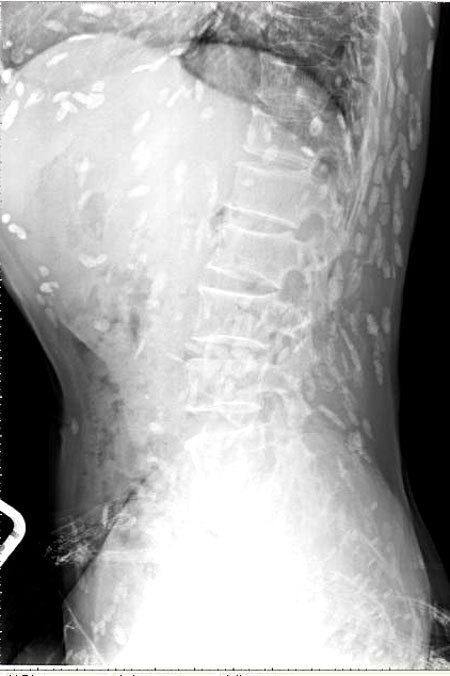

엑스레이를 찍어보니, 온몸에 촌충 같은 기생충이 퍼져있는 것이 Xray사진에 찍혔다.

기침으로 인한 고통을 호소한 환자를 진료하던 의료진은 환자의 엑스레이 사진을 보고 경악했습니다. 엑스레이 촬영물에는 여러 마리의 촌충과 유충이 가득 찍혀있는 것이었습니다.

브라질의 한 의료진이 소셜네트워크서비스(SNS)에 기생충에 감염된 엑스레이 사진을 공개했습니다. 사진에는 몸속에 있는 기생충이 죽어 석회화된 수백 개의 점 형상이 보였습니다.

특히 유충이 근육이나 뇌 조직에 침투한 모습은 매우 충격적이었습니다. 이러한 증상은 유구조충의 유충에 의한 인체감염증으로, 유구 낭미충증이라고도 불립니다.

유구낭미충증은 주로 인간의 장에 사는 촌충의 유충이 근육이나 뇌로 침투할 때 발생합니다. 이 유충은 근육과 뇌에서 낭종과 같은 결절을 형성하기도 합니다.

유구낭미충은 육류, 특히 완전히 익히지 않은 돼지고기를 섭취할 때 인체로 전염됩니다. 이 유충은 뇌나 눈에 침투하여 두통, 복통, 심한 기침, 발작, 시력 저하 등 다양한 증상을 일으킬 수 있습니다. 세계보건기구(WHO)는 유구존충 유충으로 인한 낭종이 뇌전증의 주원인이 된다고 설명하고 있습니다.

의료진은 해당 환자가 특별한 치료를 받지 않았다고 밝혔습니다. 그는 "머리, 척수, 눈에 이상이 없는 한 치료가 필요하지 않습니다"라며 "해당 물체들은 석회화되어 있어 생존 가능한 유충이 아닙니다. 불편함을 느끼지 않는다면 특별한 조치가 필요하지 않습니다"라고 말했습니다. 그러나 해당 환자의 뇌에 낭종이 있는지 확인하기 위해 MRI 검사를 기다리고 있다고 전했습니다.